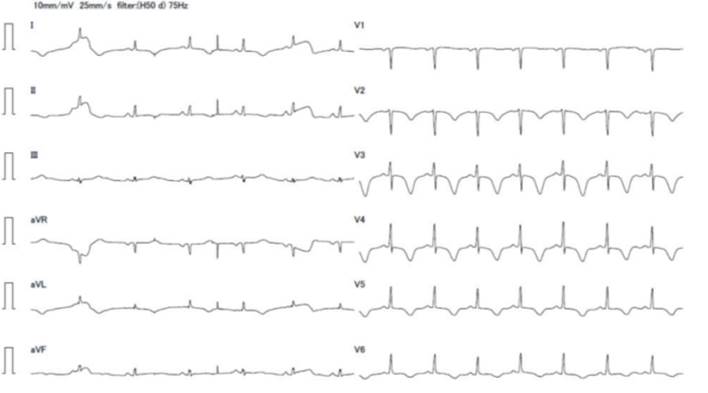

La paciente consultó en centro de salud del interior por episodio de dolor torácico retroesternal, tipo puntada, intenso, sin irradiaciones, que apareció en reposo, se acompañó de síndrome neurovegetativo, duró 30-40 minutos y cedió de manera espontánea. No presentó elementos del examen físico a destacar. El electrocardiograma (ECG) reveló ritmo sinusal, P y PR normales, eje eléctrico normoposicionado, QRS finos, ondas T negativas profundas y simétricas en cara lateral y anteroseptal, QT normal (figura 1).

Fue trasladada a centro de tercer nivel en Montevideo, arribó a las 14 horas del inicio de la sintomatología, sin dolor y con examen físico normal. En emergencia se realizó dosificación de troponinas, que estaban elevadas (4.200 ng/ml a las 16 horas del dolor y 2.700 ng/ml a las 19 horas del dolor, para un punto de corte positivo > 0,060 ng/ml). El ionograma y la función renal eran normales. Del resto de la paraclínica se destaca leucocitosis de 12.700, VES y PCR normales. El electrocardiograma no presentó cambios respecto al previo.

Los hallazgos electrocardiográficos más frecuentes son la taquicardia sinusal y alteraciones inespecíficas del segmento ST y la onda T, así como anormalidades de la conducción y arritmias. En el ecocardiograma puede aparecer disfunción sistólica global o regional y derrame pericárdico. La miocarditis fulminante a menudo se presenta como miocardio engrosado e hipocontráctil, como resultado del edema intersticial y la pérdida de contracción ventricular4.